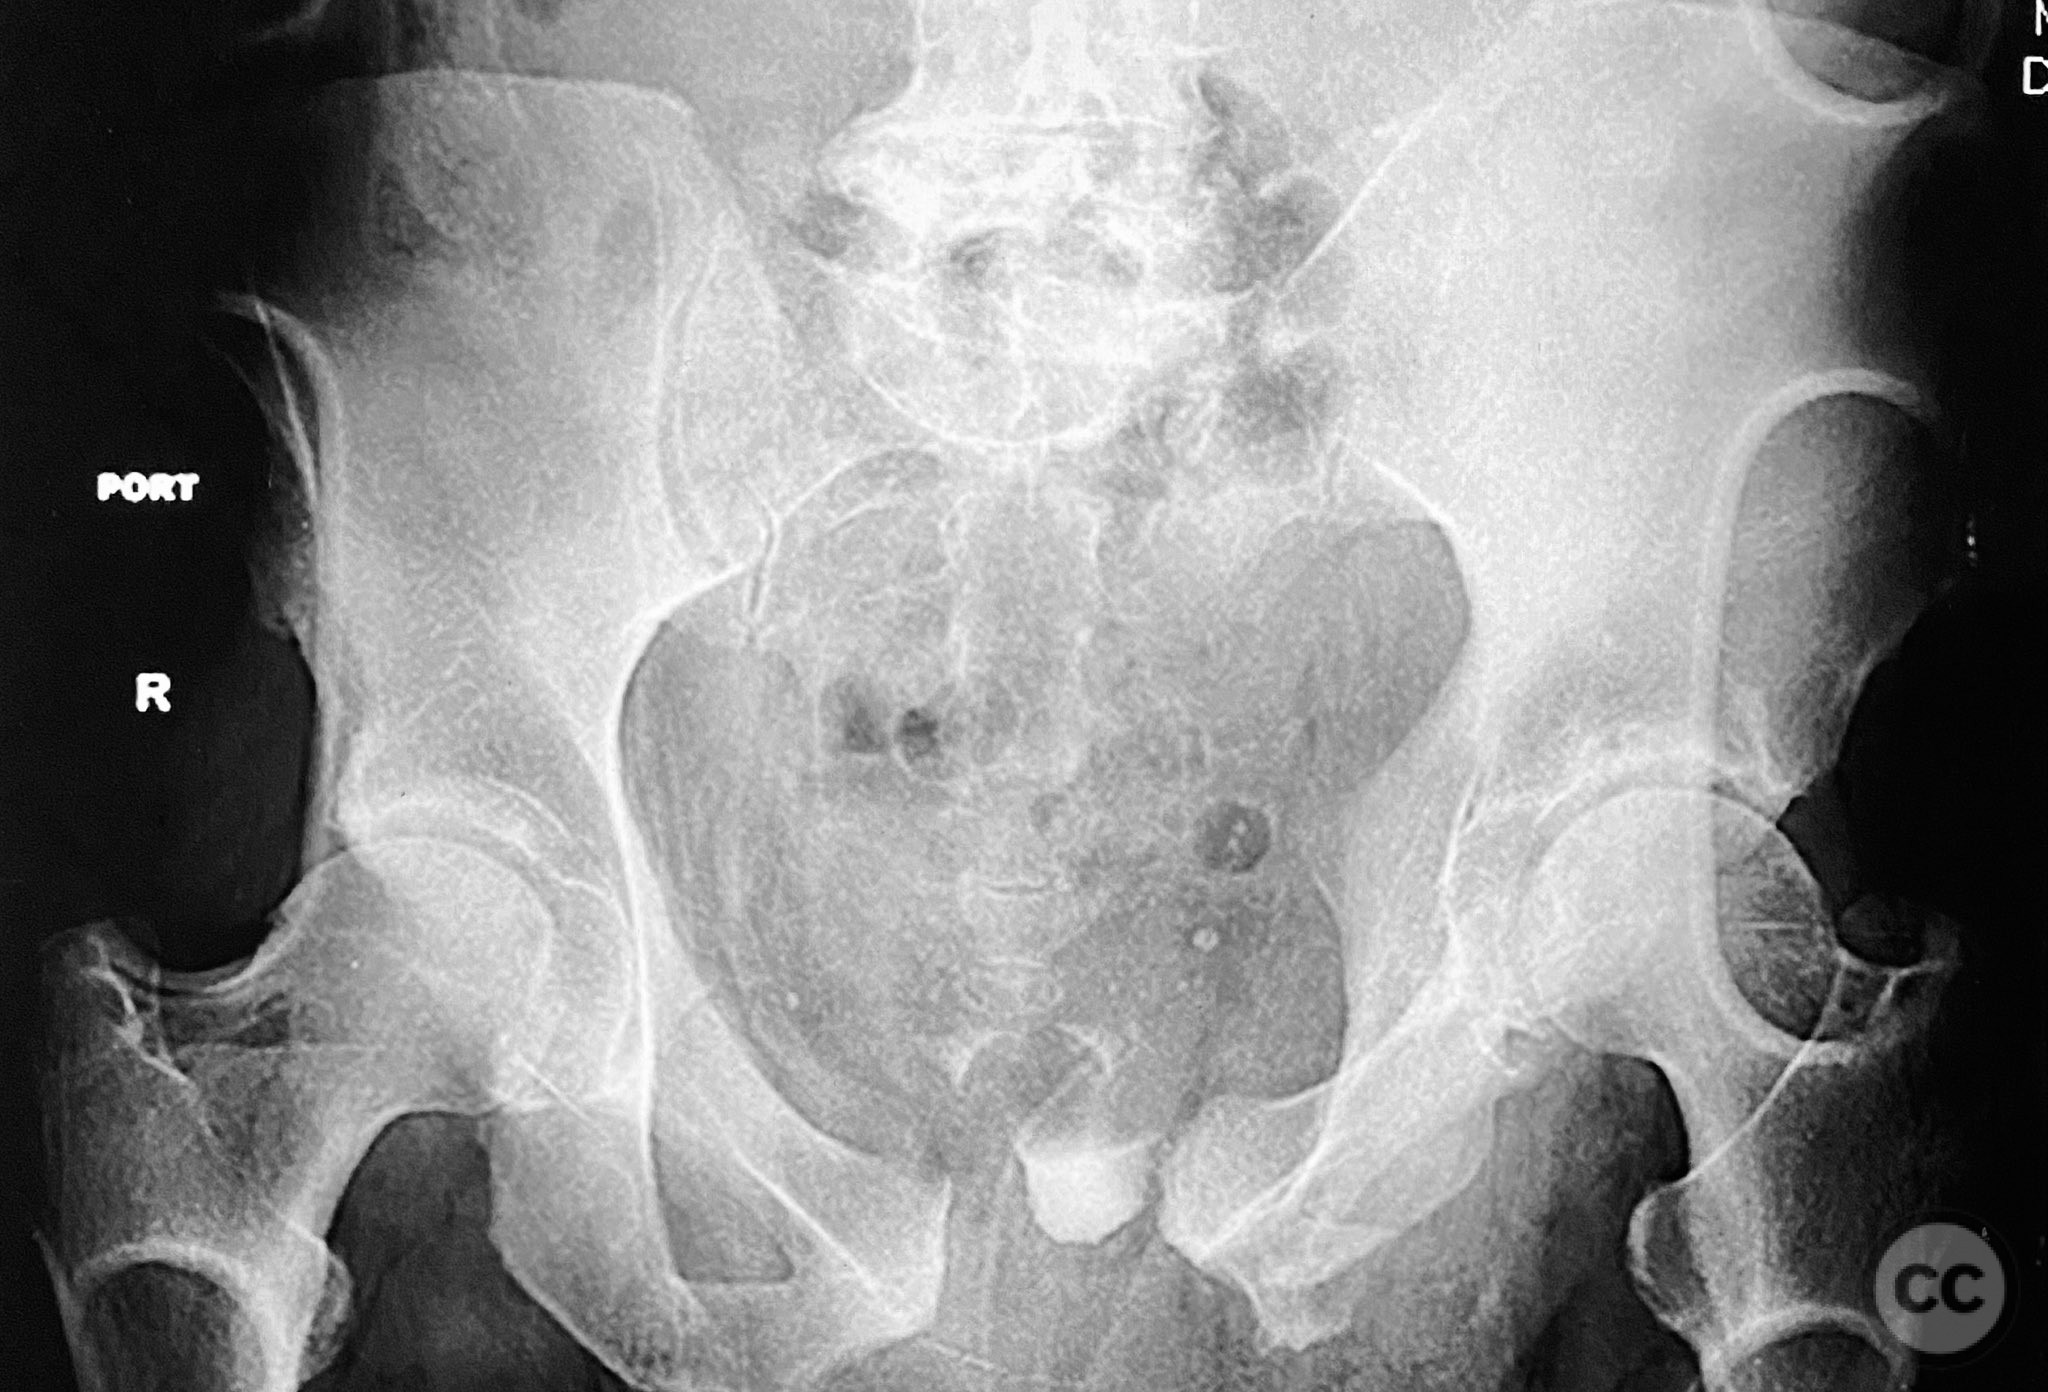

Clinical and radiological findings:  A 54-year-old male presented following a motor vehicle accident with pelvic pain. He was haemodynamically stable and neurologically intact on admission. Initial anteroposterior pelvic radiograph demonstrated disruption of the symphysis pubis, fractures of the left superior/inferior pubic rami, and a left sacral fracture. Circumferential pelvic sheeting improved patient comfort and reduced hemipelvic displacement. Skeletal traction was considered but not yet applied. Computed tomography revealed comminution and displacement of the left sacral fracture, as well as detailed characterization of the anterior ring injuries. AO/OTA classification: 61-C1.3 (displaced, combined anterior and posterior ring injury with complete instability). Young-Burgess classification: APC III.